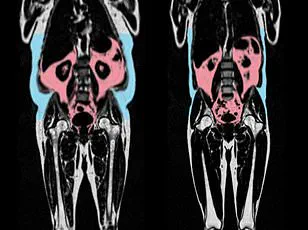

A separate study published in the European Heart Journal found that visceral fat—dangerous fat that accumulates deep within the body around organs such as the liver, stomach, and intestines—can accelerate the aging of the heart and blood vessels.

This type of fat, invisible from the outside, may explain why some slim individuals still face significant health risks.

The study found that men with an 'apple-shaped' body type, characterized by fat accumulation around the abdomen, were more likely to show signs of accelerated heart aging, while women with a 'pear-shaped' body type, storing fat around the hips and thighs, had healthier cardiovascular profiles.

These findings add another layer to the conversation about health and body composition, suggesting that body shape and the distribution of fat may be more critical than weight alone in determining heart health.